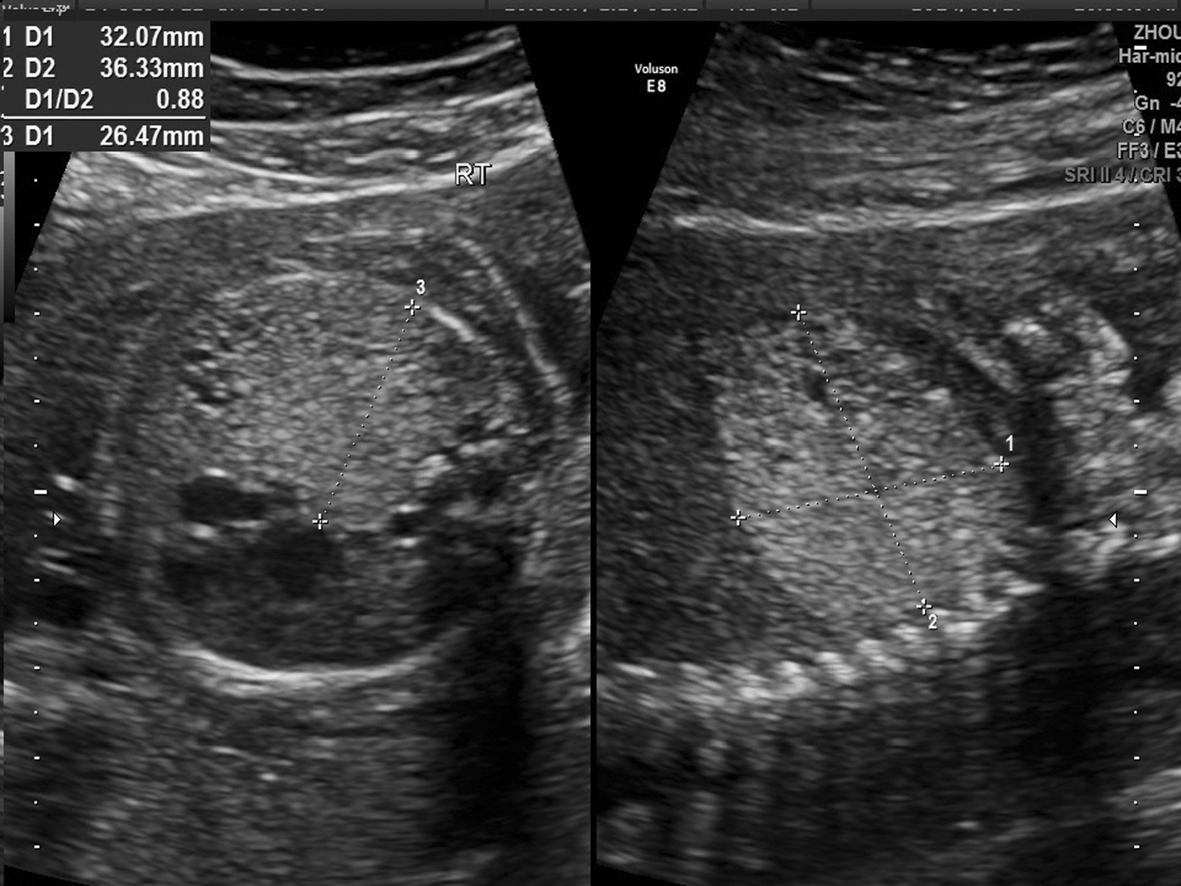

1.胎儿肺部异常 ①I型(大囊肿型):胸腔内见囊性或囊实混合性肿块,囊肿直径≥2 cm(图1);②Ⅱ型(小囊肿型):胸腔内见囊实混合性肿块,囊肿直径在5mm~2 cm间(图2);③III型(实质型或微囊肿型):胸腔内强回声实性肿物,与正常肺组织边界清晰,使用高频探头可观察到强回声实性肿块内部弥漫分布筛孔状无回声区,最大囊肿直径<5 mm(图3、4)。

图3 右侧CCAM III型,孕22周5天,胸腔发现占位性病灶